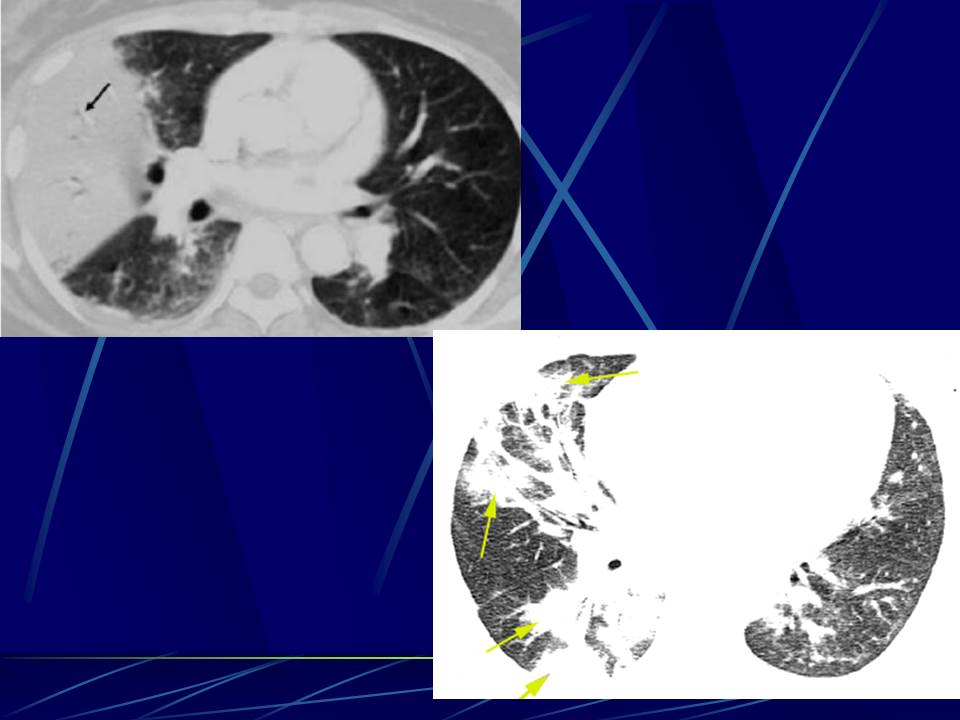

肺部真菌感染影像学分析